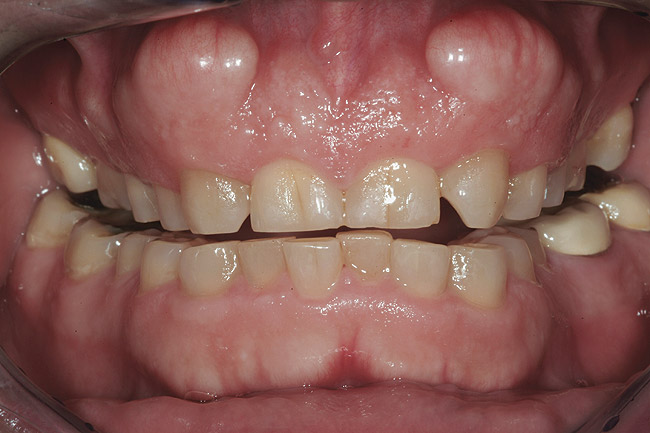

Un bărbat în vârstă de 48 ani, clinic sănătos, s-a prezentat pentru consultaţie, reclamând în principal zâmbetul său dezagreabil. Era îngrijorat cu privire la pierderea progresivă a structurii dentare pe care a constatat-o în decursul ultimilor ani şi cu privire la colorarea generalizată şi afişarea inadecvată a dinţilor şi gingiilor sale. Imaginile retractate preoperatorii relevau o formă de arcadă îngustă cu înghesuire minoră, uzură severă şi eroziune, alături de formarea unor torusuri voluminoase în regiunile maxilare vestibulare1 (fig. 1).

O fotografie iniţială a zâmbetului a evidenţiat afişarea în exces a gingiei, iar măsurătorile au dezvăluit o lungime a incisivilor centrali de 8,5mm (faţă de ideal 11,5mm).7,8

Fotografiile finale ale acestui caz au pus în evidenţă genul de rezultate care se pot obţine urmând sistemele şi tehnicile dovedite (fig. 8-11). S-au realizat obiectivele de îmbunătăţire a raportului “alb-roz” alături de cele legate de zâmbetul pacientului. Perceperea în mod clar a obiectivelor acestui caz şi capacitatea de a comunica cu acurateţe cu pacientul şi ceramistul reprezintă o parte din cheia succesului.